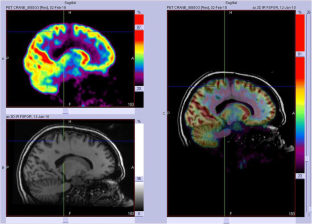

We analysed 18F-FDG PET scans from 103 consecutive patients (52 males, 7–65 years old) with histologically proven FCD2. PET and MRI data were first reviewed by visual analysis blinded to clinical information and FCD2 location. The additional value of electroclinical data and PET/MRI coregistration was assessed by comparison with pathological results and surgical outcomes.

Visual analysis of PET scans showed focal or regional hypometabolism corresponding to the FCD2 in 45 patients (44%), but the findings were doubtful or misleading in 37 patients and negative in 21. When considering electroclinical data, positive localization was obtained in 73 patients, and this increased to 85 (83%) after coregistration of PET and MRI data. Under the same conditions, MRI was positive in 61 patients (59%), doubtful in 15 and negative in 27. The additional value of PET was predominant in patients negative or doubtful on MRI, localizing the FCD2 in 35 patients (83%). Interobserver agreement correlated with the grade of hypometabolism: it was good in patients with mild to severe hypometabolism (82–95%), but moderate in those with subtle/doubtful hypometabolism (45%). The main factors influencing positive PET localization were the grade of hypometabolism and the size of the FCD2 (P < 0.0001). Misleading location (nine patients) was associated with a small FCD2 in the mesial frontal and central regions. Following limited cortical resection mainly located in extratemporal areas (mean follow-up 5.6 years), a seizure-free outcome was achieved in 94% of patients, including Engel’s class IA in 72%.

In this series, 18F-FDG PET contributed to the localization of FCD2 in 83% of patients. This high localizing value was obtained by integration of electroclinical data and PET/MRI coregistration. This approach may help improve the surgical outcome in extratemporal epilepsy, even in patients negative on MRI.